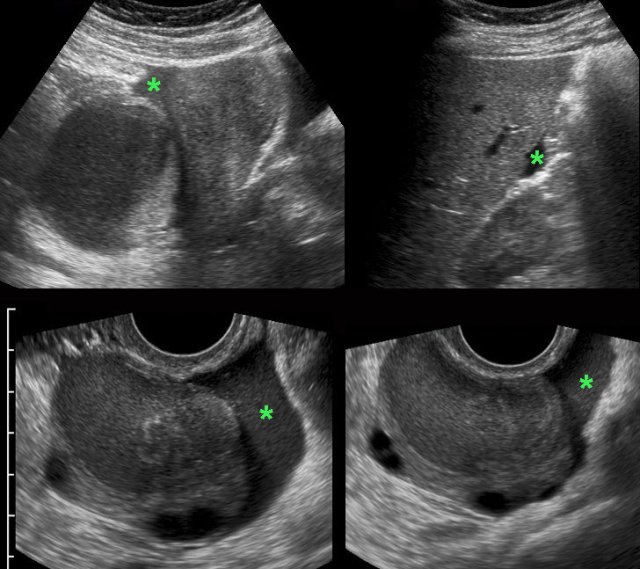

TOA case 4 (infected endometriotic cysts)

These images are of a 29-year old woman, suspected for appendicitis. CRP 185, WBC 17.

US shows a normal compressible appendix, thereby excluding appendicitis.

Large, thick-walled, septated cystic structures, filled with debris-like material, were found on both sides of the uterus (ut.), touching each other posteriorly (“kissing ovaries”).

This is somewhat suspect for bilateral infected endometrotic cysts.

The patient was treated with antibiotics and laparoscopic drainage.

There was a protracted course, but eventually regression of the abnormalities.

An MRI six months later, demonstrated all the signs of deep infiltrating endometriosis, also invading the rectum, thereby confirming the diagnosis of endometriosis.